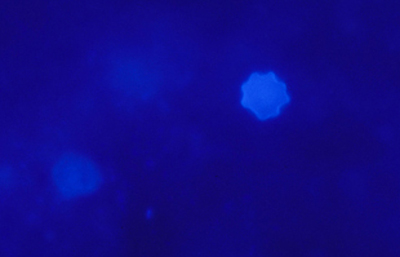

Blanco de Calcofluor

El uso del fluorocromo Blanco de Calcofluor no es excluyente de otras coloraciones, pues al ser en base acuosa no es permanente y la preparación puede lavarse en agua corriente para luego ser coloreadas con Giemsa, PAS u otras coloraciones, con el fin de reconfirmar los hallazgos microscópicos y volverlas permanentes para guardarlas.

Blanco de Calcofluor: Sobre el porta-objetos con el extendido ya fijado colocar unas gotas de Blanco de Calcofluor al 0.1% y de Azul de Evans 0.1%. Esperar 3 minutos. Cubrirlo con un cubre-objetos. Retirar con papel de filtro el exceso de líquido que se exterioriza por los bordes del cubre-objetos. Examen en el microscópio de fluorescencia. Emplear filtro excitador de 365 nm. y de emisión de 450-490 nm. Algunos autores favorecen emplear un filtro de emisión con longitud de onda más larga, fuera de la banda azul, en 520-550 nm. si bien con estas longitudes de onda la visualización de la emisión fluorescente es menos intensa.

Las imágenes de Acanthamoebas muestran una cápsula circular u ondulada, refringente de color azulado o verde manzana, notablemente más intensa que los materiales y tejidos que la rodean. Suelen medir de 12 a 16 µm de diámetro. El contenido del quiste es azul tenue. (Figura 37 , 38, 39 y 40)

Fig. 37 Blanco de Calcofluor (CW). Original x160

Fig. 38 CW, Original x250

Fig. 39 CW, Original x160

Fig. 40 CW, Original x160